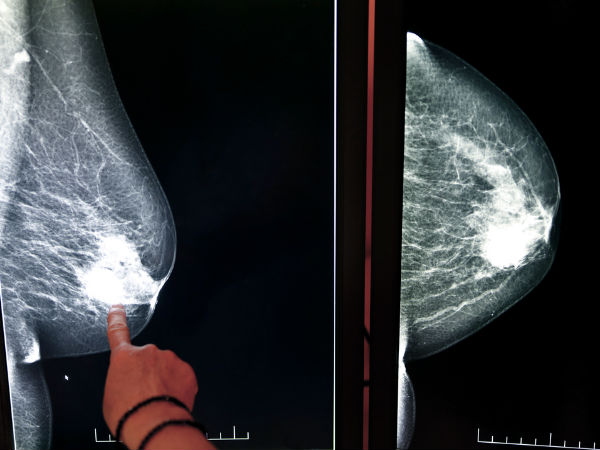

गर्भावस्था और ब्रेस्ट कैंसर के खतरे के बीच संबंध

अध्ययनों से पता चला है कि किसी महिला को ब्रेस्ट कैंसर होने का खतरा उसकी ओवरीज़ द्वारा उत्पन्न किये जाने वाले हार्मोंस से संबंधित होता है। गर्भावस्था और ब्रेस्टफीडिंग का सीधा प्रभाव ब्रेस्ट की कोशिकाओं पर पड़ता है ताकि उनमें कुछ अंतर आए या वे परिपक्व हो सकें और दूध बना सकें। कुछ शोधकर्ताओं का ऐसा मानना है कि ये परिवर्तित कोशिकाएं ही कैंसर की कोशिकाएं बन जाती हैं जबकि अपरिवर्तित कोशिकाओं के कैंसर की कोशिकाओं में बदलने का खतरा बहुत कम होता है। 35 की उम्र के बाद मां बनने के लिए 35 टिप्स

ऐसी महिलायें जो बहुत कम उम्र में मां बन जाती हैं उनमें ब्रेस्ट कैंसर होने का खतरा बहुत कम होता है। ऐसी महिलायें जिन्होंने 30 वर्ष की उम्र के बाद पहले बच्चे को जन्म दिया है उनमें ब्रेस्ट कैंसर होने की संभावना उन महिलाओं से अधिक होती है जिन्होंने कभी भी बच्चे को जन्म नहीं दिया है।

महिला की पहली गर्भावस्था के बाद ब्रेस्ट कैंसर होने की संभावना बढ़ जाती है परन्तु यह धीरे धीरे कम हो जाती है तथा बाद की गर्भावस्था पर इसका कोई प्रभाव नहीं पड़ता।

महिलाओं द्वारा पहले बच्चे को जन्म देने की उम्र हर पांच साल में बढ़ रही है जिसके कारण महिलाओं को ब्रेस्ट कैंसर होने की संभावना 7% से बढ़ रही है।